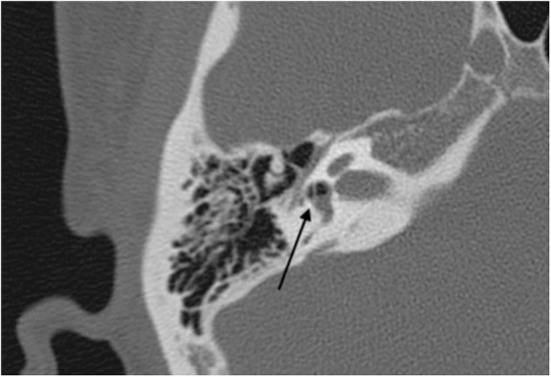

患者再次接受卧床休息和皮质类固醇治疗。然而,经过保守治疗后,眩晕和严重听力损失没有得到缓解。于第17天进行外淋巴瘘修补手术。手术在全麻下进行,经外耳道入路,可以观察到镫骨足板中央有一个直径为0.5毫米的骨缺损,由膜组织覆盖,并且在膜上发现了一处撕裂(图3)。